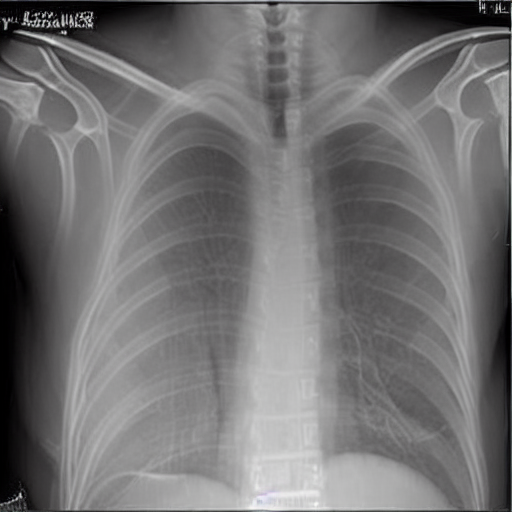

Input Prompt:

"I've been feeling really out of breath lately, especially when I'm walking up a flight of stairs or doing some light exercise. It's like my chest gets tight and I can't catch my breath. "

Output:

The model generates a chest X-ray image that corresponds to symptoms of a potential pulmonary issue.